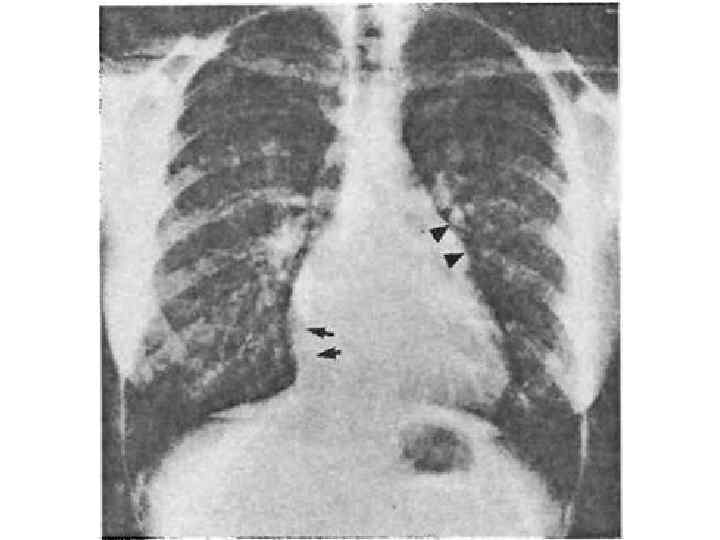

Механизмы компенсации 1. Повышается давление в полости левого предсердия (от 5 мм рт. ст. в норме до 20– 25 мм рт. ст. ); увеличивается разность (градиент ) давления левого предсердия — левого желудочка, что облегчает прохождение крови через суженное атриовентрикулярное отверстие. 2. Удлиняетс я систола левого предсердия; кровь в левый желудочек поступает в течение более длительного времени. 3. Гипертрофия мышцы левого предсердия — является следствием длительной перегрузки предсердия давлением. 4. Прогрессирующее уменьшение площади левого атриовентрикулярного отверстия вызывает дальнейший рост давления в левом предсердии, что приводит к ретроградному повышению давления в легочных венах и капиллярах. Повышается давление в легочной артерии, развивается пассивная, ретроградная, венозная, посткапиллярная легочная гипертензия. Давление в легочной артерии 30– 60 мм рт. ст. (в норме до 25 мм рт. ст. ). Развивается гипертензия правого желудочка. 5. Дальнейший рост давления в левом предсердии и легочных венах вследствие раздражения барорецепторов вызывает рефлекторное сужение артериол (рефлекс Китаева). Это ведет к значительному повышению давления в легочной артерии (60– 200 мм рт. ст. ), развивается активная, артериальная, прекапиллярная гипертензия. Рефлекс Китаева выполняет защитную роль, предохраняя легочные капилляры от чрезмерного повышения давления и выпотевания жидкой части крови в полости альвеол.

Течение митрального стеноза I стадия — одышки нет в покое и при нагрузке, больные полностью компенсированы. II стади я — при знаки нарушения кровообращения в малом круге, выявляющиеся только при физической нагрузке. III стадия — в малом круге выраженные признаки нарушения кровообращения; в большом круге — начальные признаки застоя. IV стадия — выраженные признаки застоя в малом и большом кругах кровообращения. V стадия — дистрофическая.